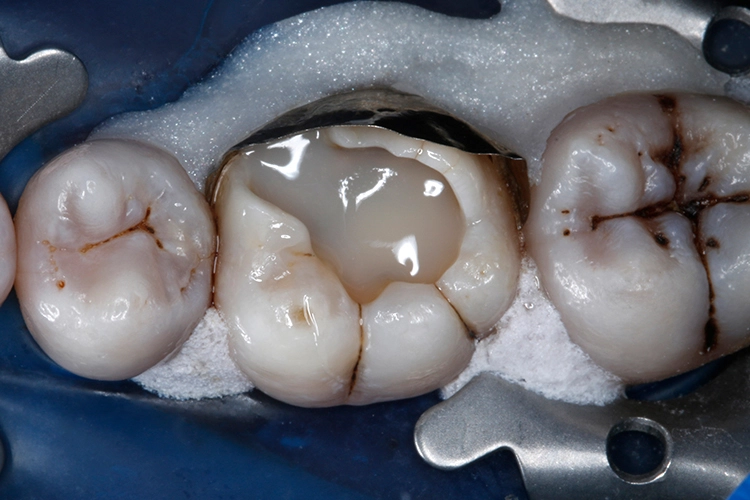

Nachfolgend wurde mit dem nächsten Inkrement VisCalor das restliche Kavitätenvolumen (maximale Schichtstärke: 2 mm) komplett aufgefüllt (Abb. 21). VisCalor kühlt innerhalb weniger Momente nach Kontakt mit dem Zahn durch Wärmeleitung (Konduktion) schnell wieder auf Mundhöhlentemperatur ab und nimmt somit wieder eine hochviskose Konsistenz an (Abb. 22), die eine Modellation der Kauflächenanatomie erleichtert.

Nach Abnahme des Kofferdams wurde die höckerersetzende direkte Kompositrestauration sorgfältig mit rotierenden Instrumenten (okklusal) und abrasiven Scheibchen (lingual) ausgearbeitet. Danach wurde mit diamantimprägnierten Silikonpolierern (Dimanto, VOCO) eine glatte und glänzende Oberfläche der Restauration erzielt.